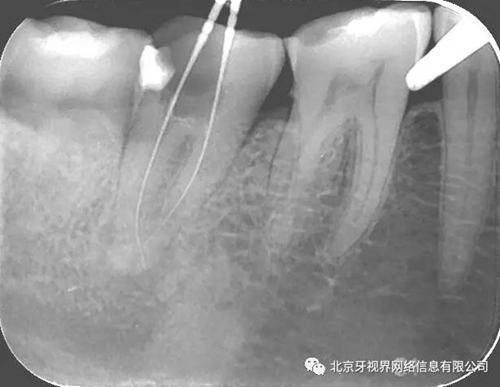

輔助檢查:15根尖周低密度影像,根尖1/3向近中彎曲

(1)15根尖周低密度影像結(jié)合查體診斷根尖周炎,根尖中下段明顯彎曲,能否疏通全長,順利抵達(dá)根尖區(qū)為術(shù)者首要考慮。

最后附帶近期彎曲根管的圖片